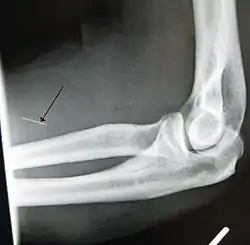

موقع الحقن المفضل هو صدع الكوع (أي الوريد الحجاجي الأوسط) ، على يد المستخدم غير المكتوبة. يختار المستخدمون الآخرون استخدام الوريد الباسيليكي ؛ في حين أنه قد يكون من الأسهل "الضرب" ، يجب توخي الحذر حيث يعمل اثنان من الأعصاب بالتوازي مع الوريد، مما يزيد من فرصة تلف الأعصاب، وكذلك فرصة "النك" الشرياني. [5]